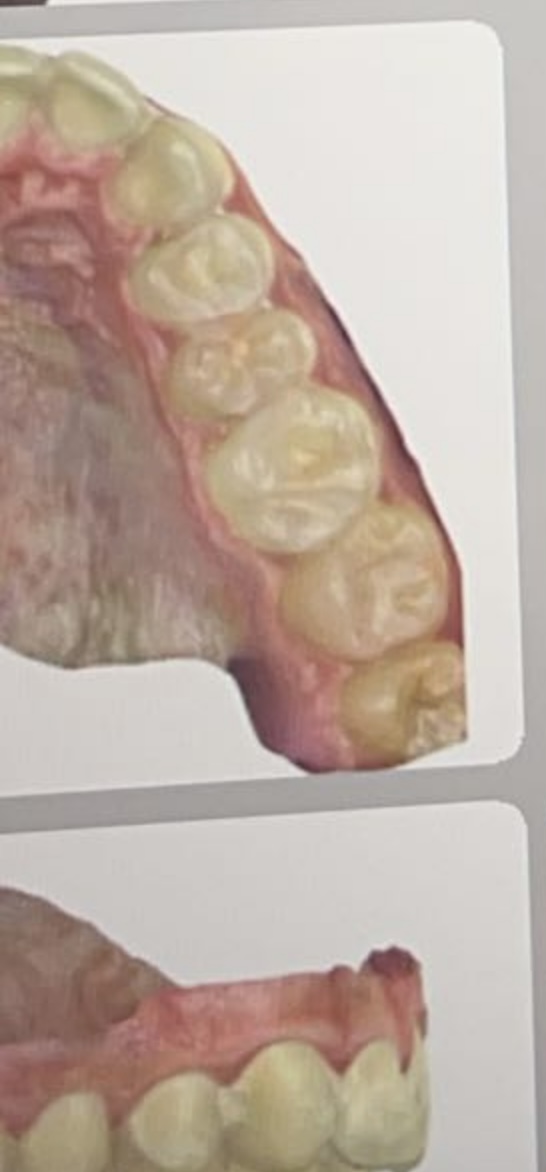

I feel mutilated tbh they yanked these and they looked fine wisdom teeth

Yeah I got them taken out did they look fine? They said they wanted them removed for Invisalign and there was a tiny flap of gum over two of themthere is no way u got ur wisdom teeth taken out? did they hurt or no

this?Yeah I got them taken out did they look fine? They said they wanted them removed for Invisalign and there was a tiny flap of gum over two of them

I think I got fucked. I had an over bite so they wanted to take them out for some reasonthis?

View attachment 3235984View attachment 3235985

Yeah the wisdom teeththis?

View attachment 3235984View attachment 3235985

You dont fix overbite by pulling teethView attachment 3235974

I feel mutilated tbh they yanked these and they looked fine wisdom teeth

no nigga, jus bone loss ig from healthy teeth removal. I was looking at a dentist in Boston that can do wisdom tooth replacement but it cost like 15kIs your overbite fixed?

They said if I wanted future orthodontic work it needed to be done…. And the ortho was weird as fuck tbh. Idk it was all shady and then they just pulled my shit and said the gums were impacted slightly on the bottom and I would need to get the tops removed because of Supra eruption apparently. So they ended up pulling all 4 healthy teeth. It was a lot of bullshutThey pulled your teeth for 0 reason then ?!? I thought they did with the excuse of fixing your overbite which would still be dumb

Idk what to do tbh, they lowkey supported my face, the bottom ones were covered by a tiny flap of gum very tiny so they used that as an excuse to remove them all. I’m talking to this girl who rly likes me tho so I don’t rly have a choice but to keep pushing for her and get surgery or sum to look better. I think it will cause bone loss tbh because once the ale ridge is gone the face might lose support. Idk manno